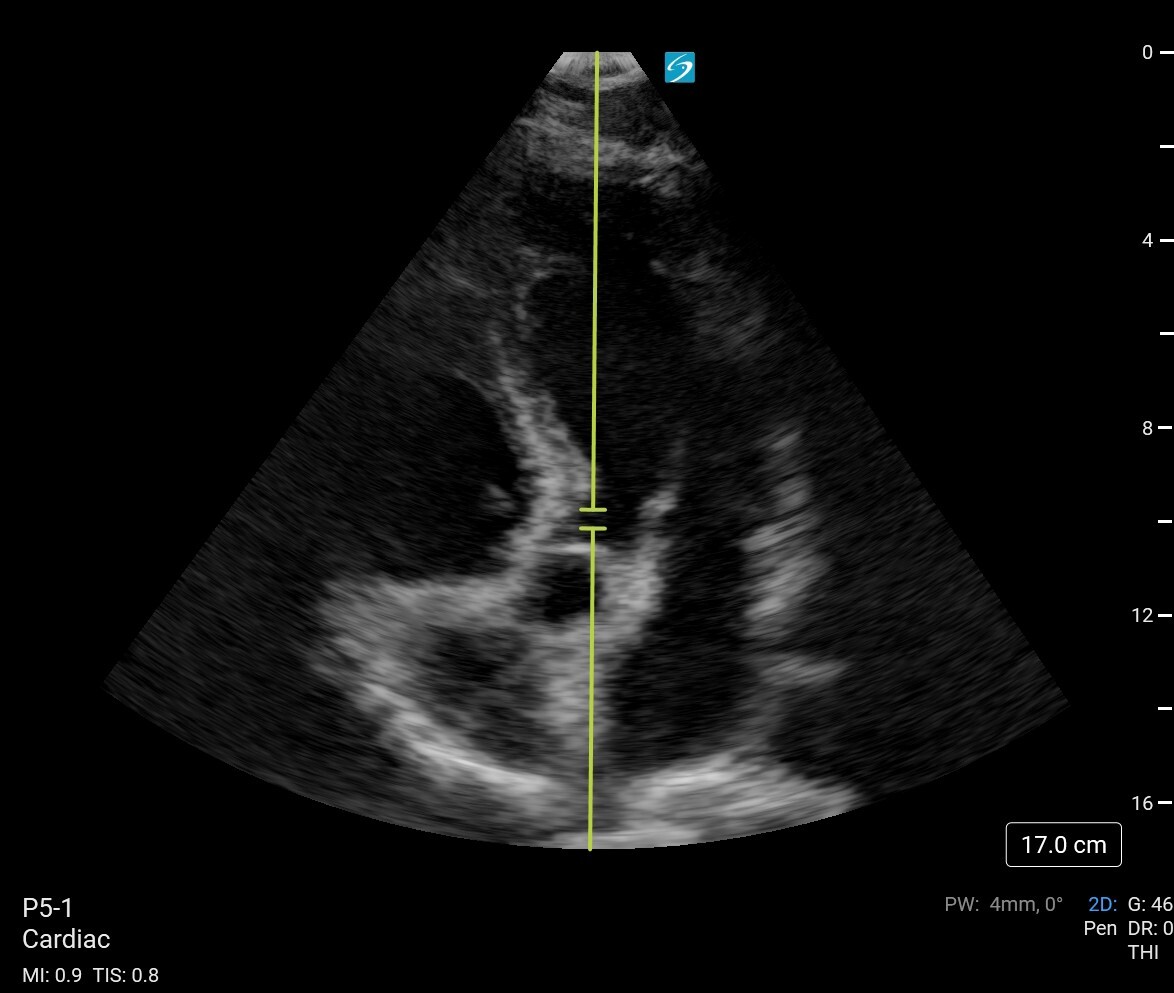

Cardiac 2 Determination of Stroke Volume VTI Apical 5 Image